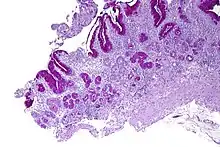

| Micrograph showing nodular enterochromaffin-like cell hyperplasia, as demonstrated with chromogranin A immunostaining, in the body of the stomach. Parietal cells are not readily apparent. These changes are in keeping with autoimmune metaplastic atrophic gastritis, a histologic correlate of vitamin B12 deficiency anemia. | |

PA may be considered as an end stage of autoimmune atrophic gastritis, a disease characterised by stomach atrophy and the presence of antibodies to parietal cells and intrinsic factor.[36][37] Autoimmune atrophic gastritis, is localised to the body of the stomach, where parietal cells are located.[34] Antibodies to intrinsic factor and parietal cells cause the destruction of the oxyntic gastric mucosa, in which the parietal cells are located, leading to the subsequent loss of intrinsic factor synthesis. Without intrinsic factor, the ileum can no longer absorb the B12.[38] Atrophic gastritis is often a precursor to gastric cancer.[37]